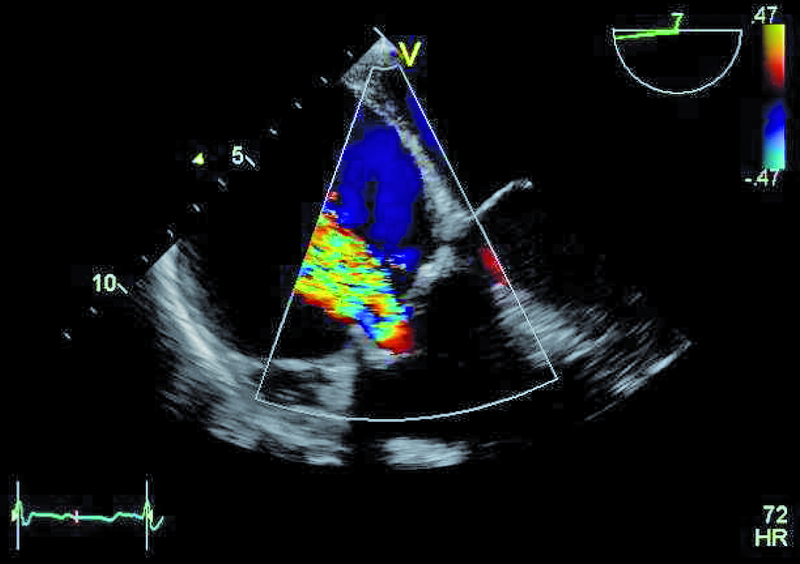

Szczegóły oceny układu krążenia z okresu przeprowadzanych operacji nie były znane. Można było jedynie przypuszczać, że śluzak prawej komory mógł zaburzać funkcję zastawki trójdzielnej, a jego resekcja pozostawiła stopniowo narastającą nieszczelność zastawki. Wymiana zastawki na biologiczną była konieczna, ale spowodowała dalsze problemy u chorego. Degeneracja zastawek biologicznych u osoby młodej może postępować dynamicznie, nawet bez obecności dodatkowych czynników nasilających to zjawisko, jak niewydolność nerek czy nadczynność przytarczyc. Kolejnym czynnikiem, poza wiekiem, wpływającym na odpowiedź immunologiczną, może być samo ujście trójdzielne, w którym procesy wapniowo-fosforanowe w odpowiedzi na rozciąganie płatków są silne. Warto także nadmienić, że zastawki biologiczne stentowe, jak użyta w tym wypadku, charakteryzują się szybszym tempem zwyrodnienia niż zastawki bezstentowe. Rozpoznanie strukturalnego zwyrodnienia bioprotezy w ujściu trójdzielnym nie powinno nastręczać trudności. Wczesnymi objawami procesu jest pogrubienie i usztywnienie płatków, które stają się w obrazie ultradźwiękowym jaśniejsze i nieregularne w zarysie (ryc. 1, 2). Ponieważ proces postępuje, włóknienie i zwapnienia obejmują najpierw spoidła, a następnie całe płatki i pierścień zastawki. W przedstawionym przypadku zwyrodnienie prowadzi zarówno do stenozy, jak i niedomykalności. O stenozie zastawki w ujściu trójdzielnym zawsze należy myśleć, gdy gradient średni napływu przekracza 6 mm Hg (ryc. 3). Niedomykalność trójdzielna uważana jest za istotną, kiedy talia strumienia ma szerokość co najmniej 6 mm (ryc. 4). Warto dodać, że rejestrowane zmiany hemodynamicznie są podobne do tych, jakie obserwuje się w natywnej zastawce trójdzielnej np. w rzadkim uszkodzeniu poreumatycznym. Chory ma wskazania do kolejnej interwencji kardiochirurgicznej i operacja w tym wypadku nie powinna być odkładana, żeby nie doprowadzić do narastającej niewydolności jam prawego serca. By uzupełnić ocenę, zarejestrowano projekcję na drogę odpływu prawej komory (ryc. 5). Wykluczono cechy nadciśnienia płucnego i niedomykalność zastawki płucnej. Zwrócono uwagę na istotnie poszerzone jamę prawego przedsionka i żyłę główną dolną (ryc. 6), odpowiadające nieprawidłowościom w badaniu fizykalnym – hepatomegalii i obrzękom obwodowym. Poza operacją można rozważyć wykonanie zabiegu techniką przezcewnikową i wszczepienie zastawki Edwards SAPIEN lub Melody (valve-in-valve). W tym wypadku na decyzji o leczeniu operacyjnym zaważyły jednak preferencja chorego i doświadczenie ośrodka.